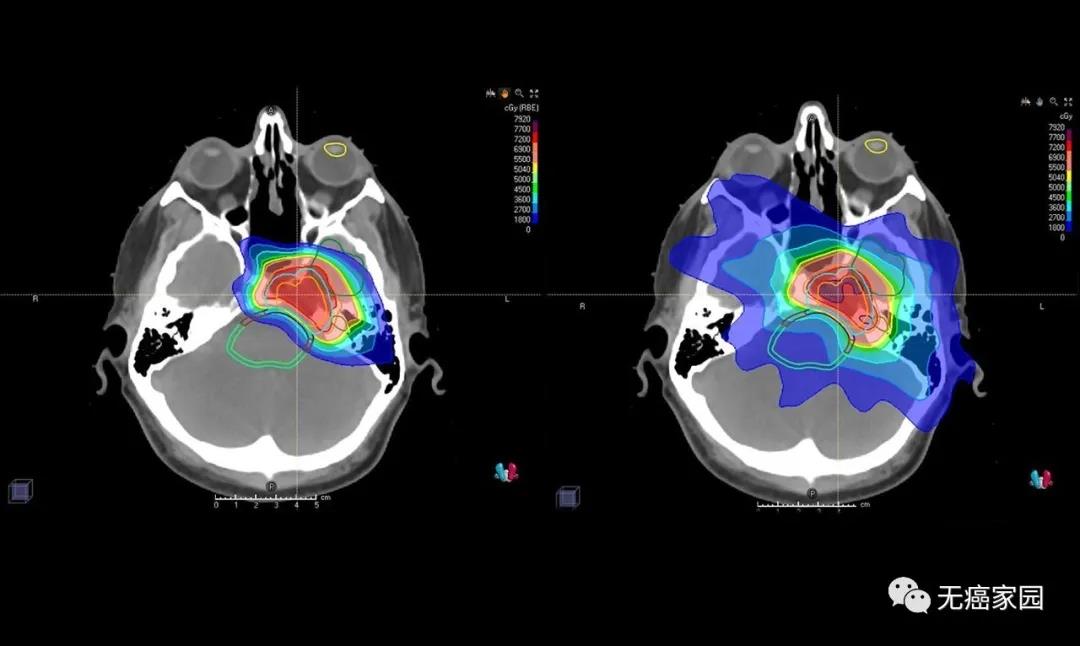

长期以来,人们都知道传统放疗使用的X射线(也称为光子)疗法会导致各种副作用,比如食管癌的放疗会造成不同程度的吞咽不适,脑瘤的放疗会导致精神不振等症状,但实际上接受...